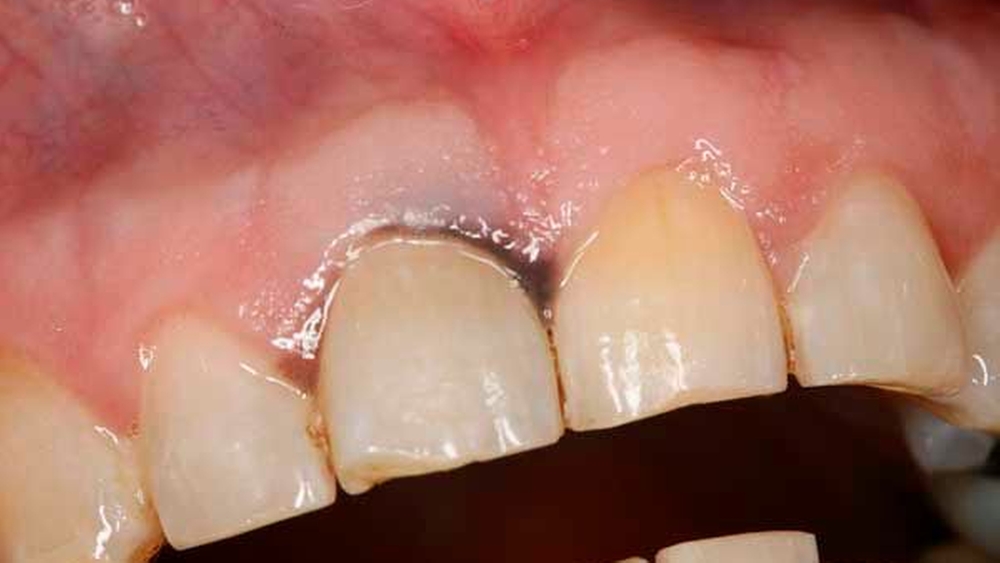

Nach drei Monaten war erneut eine circa 2 mm x 2 mm große schwärzliche Mundschleimhautveränderung in regio 012 auffällig (Abbildung 4). Die Raumforderung inklusive einer kortikalen Knochenspange des Alveolarkamms und des Os palatinum von regio 13 bis regio 23 wurde großflächig reseziert. Histopathologisch wurde ein R0-reseziertes Rezidiv des vorbekannten Melanoma in situ bestätigt, eine tiefere Tumorinfiltration über die Basalmembran hinweg oder sogar bis in den ortsständigen Knochen konnte ausgeschlossen werden.

Nach sekundärer Granulation der Exzisionswunde erfolgte die Insertion von zwei Implantaten in den regiones 12 und 21 (Abbildung 5). Da eine zeitnahe Radiatio im weiteren Verlauf nicht ausgeschlossen werden konnte, wurde auf eine Augmentation des zuvor teilresezierten Alveolarkamms verzichtet, um eine festsitzende Implantatversorgung nicht zu gefährden. Weitere sechs Monate später trat erneut ein Rezidiv im Bereich des harten Gaumens auf (Abbildung 6), das wiederum ausgedehnt im Sinne einer R0-Situation exzidiert wurde. Zusätzlich wurden die zuvor inserierten Implantate im gleichen Eingriff freigelegt (Abbildung 7).